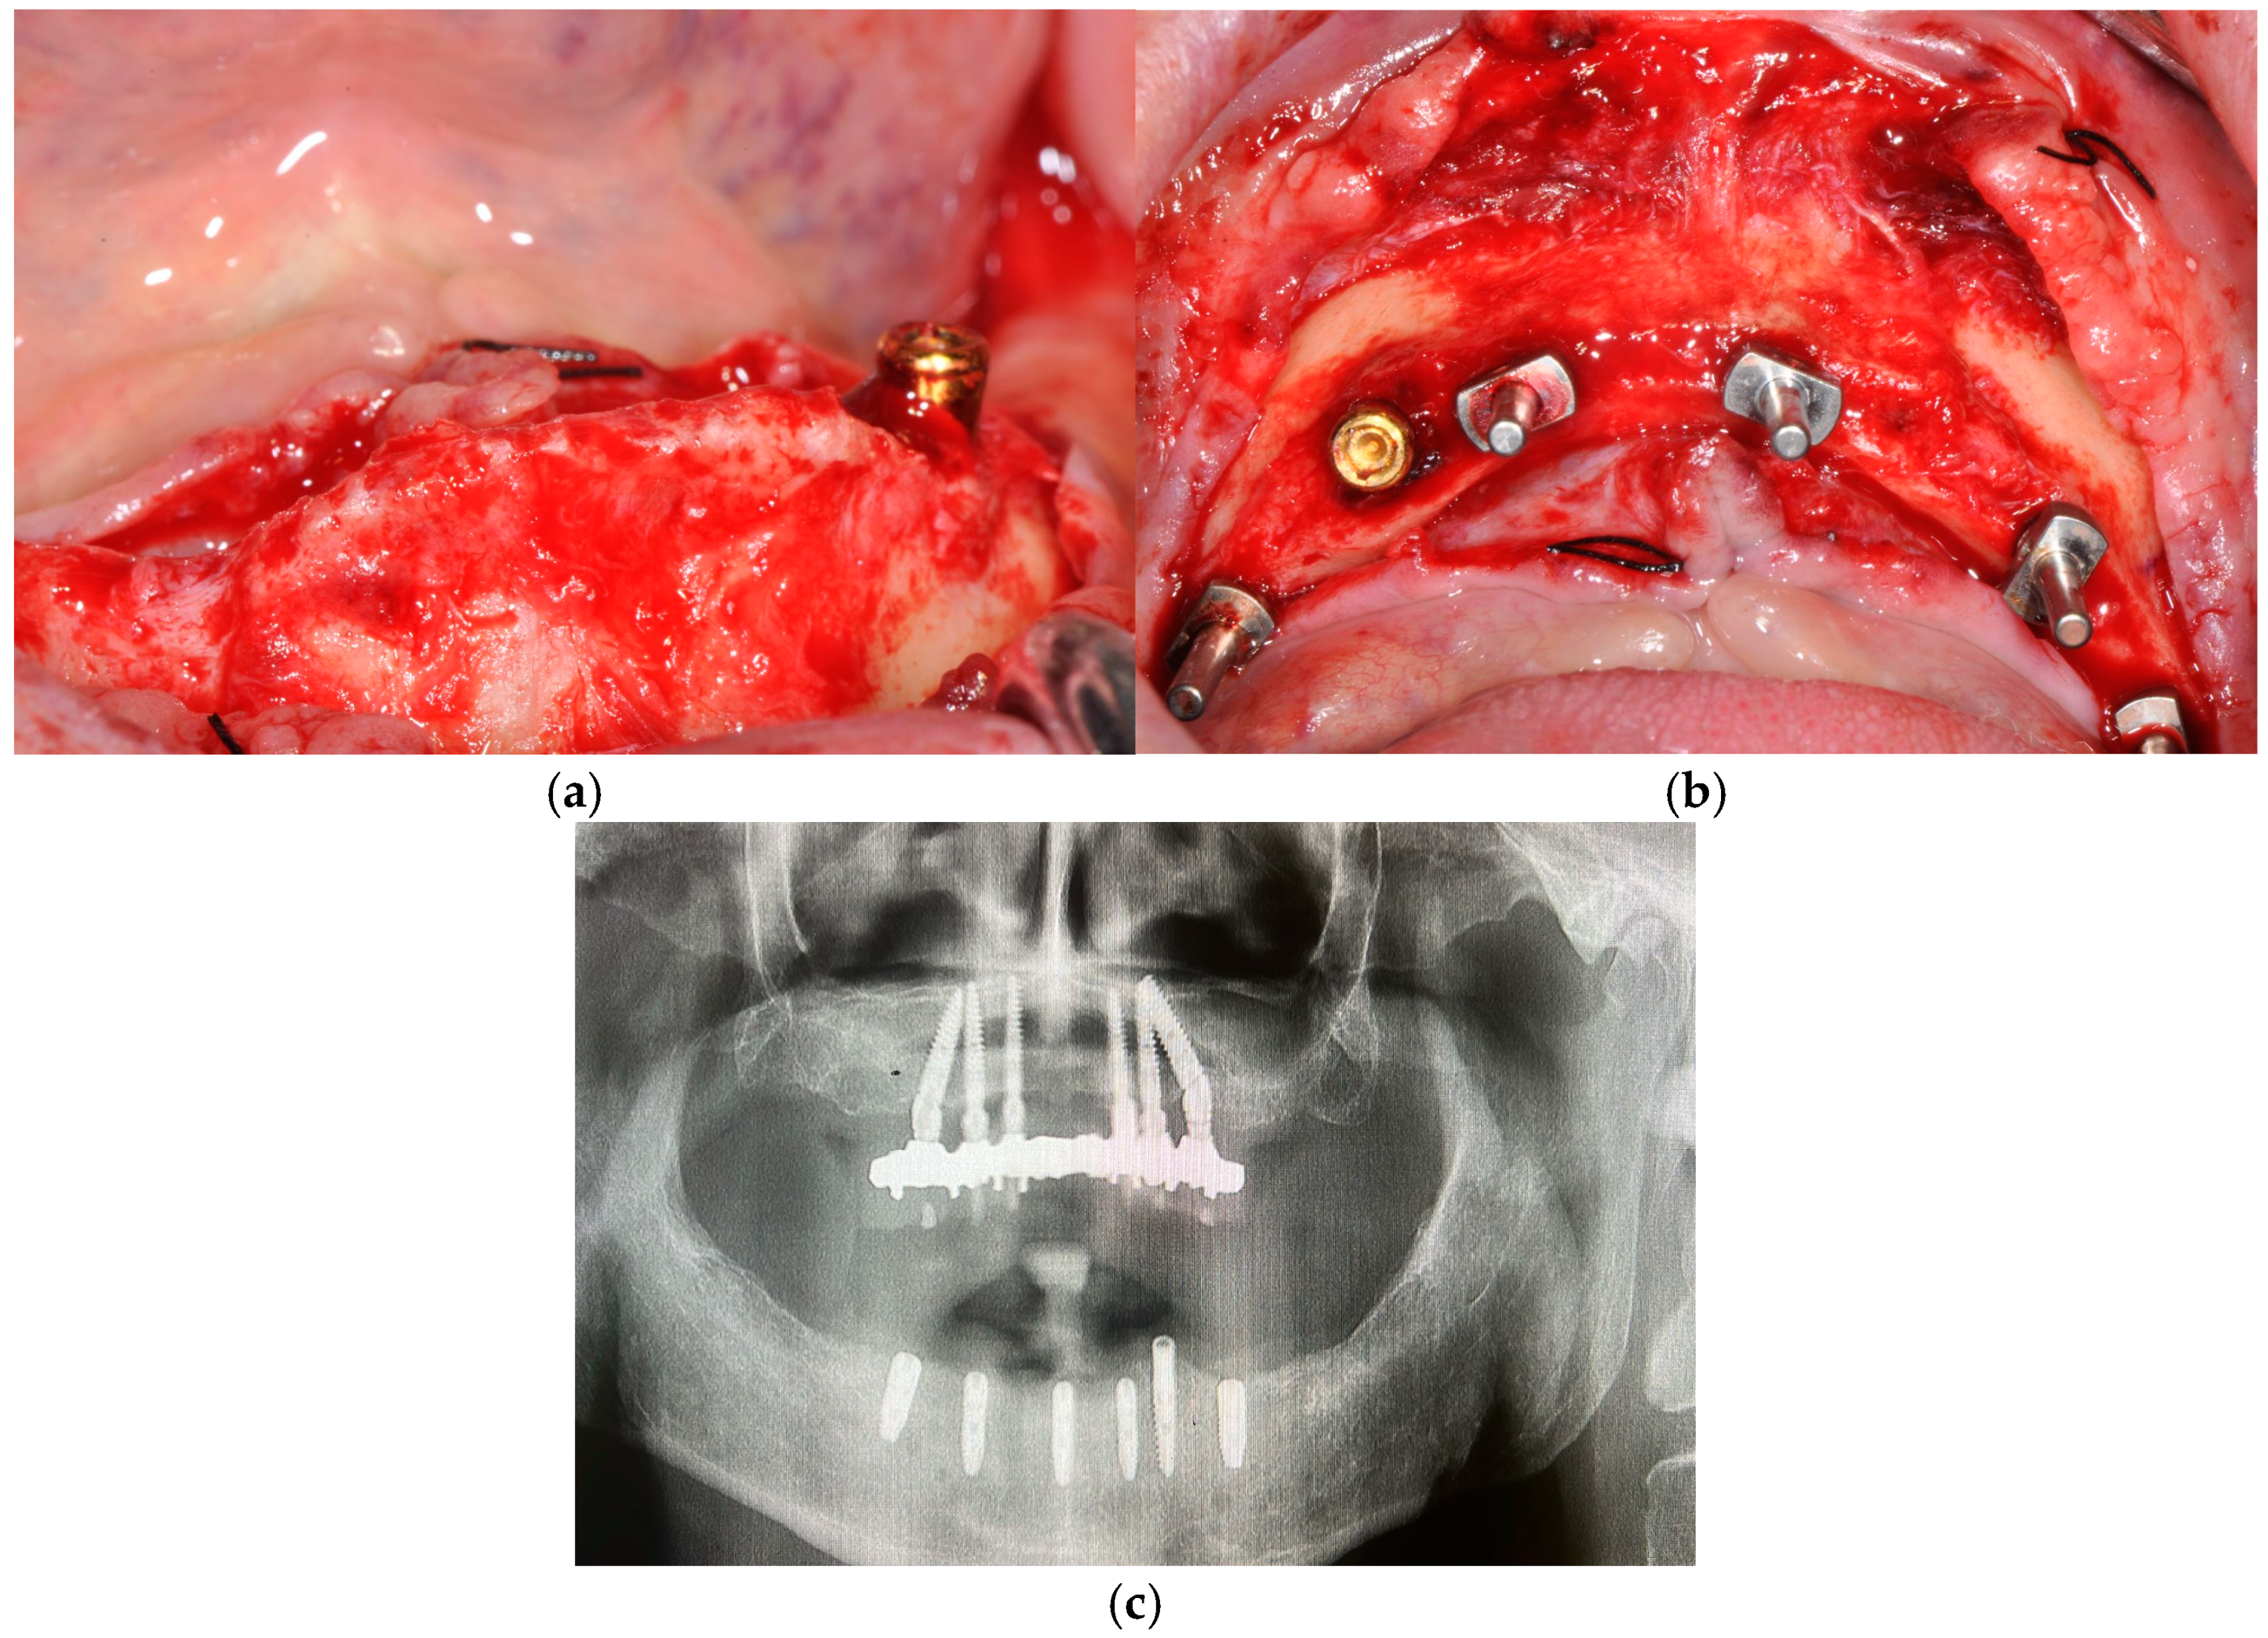

3. Case Presentation